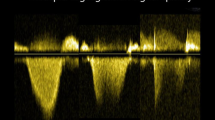

Doppler interrogation of the proximal pulmonary artery was performed either in parasternal long-axis outflow and/or the parasternal short-axis (Fig. 1A) in order to exclude pulmonic stenosis and to assess pulmonary artery flow; for patients with poor acoustic parasternal window short-axis subcostal view was preferred (Fig. 1B). Pulmonary artery flow was evaluated by placing the pulsed-wave Doppler sample volume at the pulmonary valve annulus: PAAT was calculated as the interval between the onset of ejection and the peak flow velocity. PAAT have also been indexed by RV ejection time (RVET) [13] and heart rate (HR), dividing its value for square root of RR interval [14, 15].

Pulmonary artery acceleration time (PAAT, dashed red line) and right ventricular ejection time (RVET, yellow brace) measurement in parasternal short-axis view (A) and subcostal view (B). PAAT is calculated as the time interval between the onset of systolic pulmonary artery flow and its peak flow velocity; RVET is measured from the onset to the end of pulmonary artery Doppler spectrum. For further adjustment, sPAP was derived on the basis of the linear correlation linking PAAT to TRVmax as follows: log10(sPAP) = −0.004 (PAAT) + 2.1 [8]. Mean PAP (mPAP) can be estimated using the following formulae proposed by Dabestani et al. [28]: if PAAT ≥ 120 ms, mPAP = 79 – (0.45 * PAAT); if PAAT < 90 ms, mPAP = 90 – (0.62 * PAAT)